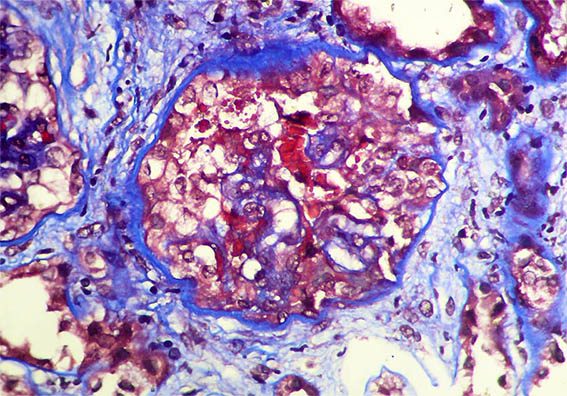

Figura 5. Tricrómico de Masson, X400.

Figura 6. Tricrómico de Masson, X400. Hiperplasia de podocitos o semiluna (?).